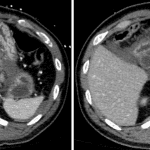

- Complex hepatic laceration measuring 6 cm in depth predominantly involving hepatic segments 2 and 3 without evidence of active hemorrhage

- Complex laceration involving the superior pancreatic body with surrounding parenchymal contusion

- Adjacent hemorrhage with a small contrast density focus which enlarges on delayed phase images

- Moderate volume of hemoperitoneum, primarily in the lesser sac, perihepatic space, and subhepatic space

Complex left hepatic lobe laceration measuring 6 cm in depth without evidence of active hemorrhage at this location. Moderate surrounding hemoperitoneum.

Complex laceration involving the superior pancreatic body with surrounding parenchymal contusion and adjacent hematoma in the anterior pararenal space and lesser sac with small focus of active hemorrhage. Given extensive involvement of the pancreatic body, a pancreatic duct injury is not excluded.